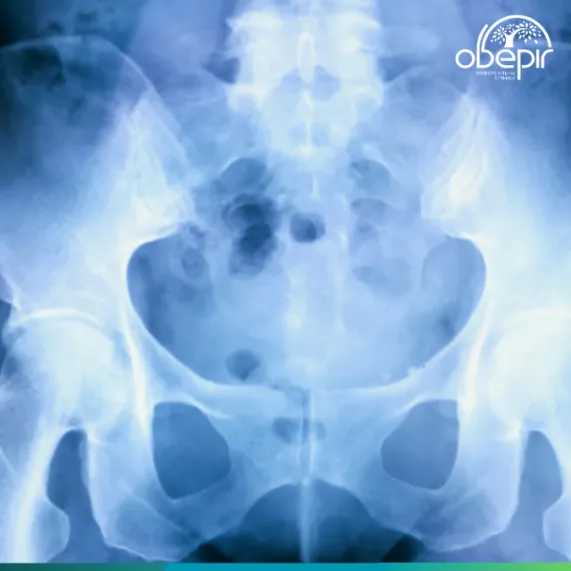

Денситометрия (Двухэнергетическая рентгеновская абсорбциометрия - DEXA/ДРА): Это "золотой стандарт" для диагностики остеопороза. Метод позволяет измерить минеральную плотность костной ткани (МПКТ) в различных участках скелета (чаще всего в бедренной кости и поясничном отделе позвоночника) и оценить риск переломов. Результаты сравниваются с нормативными показателями для молодых взрослых (Т-критерий) и для людей того же возраста (Z-критерий)4.

Рентгенография: Позволяет выявить переломы, но для диагностики остеопороза как такового менее эффективна, поскольку значительные изменения костной плотности становятся заметными лишь тогда, когда потеряно более 30% костной массы.